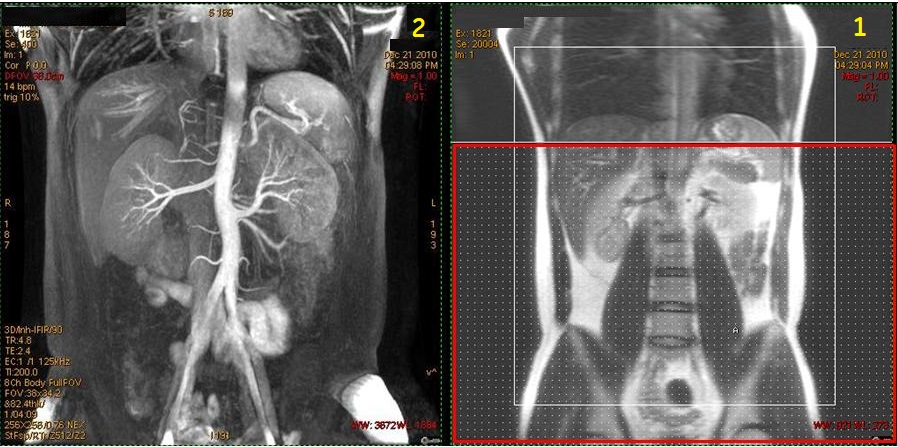

Figure 1. 1.5T Inhance 3D Inflow IR with Respiratory Triggering

Figure 4. Coronal localizer with IR band and resultant coronal renal image

Table 2. Image legend

NumberDescription

1Coronal localizer with large axial IR band (red box) applied inferior to saturate venous flow.

2Resultant Inhance Inflow IR coronal image of renal artery .